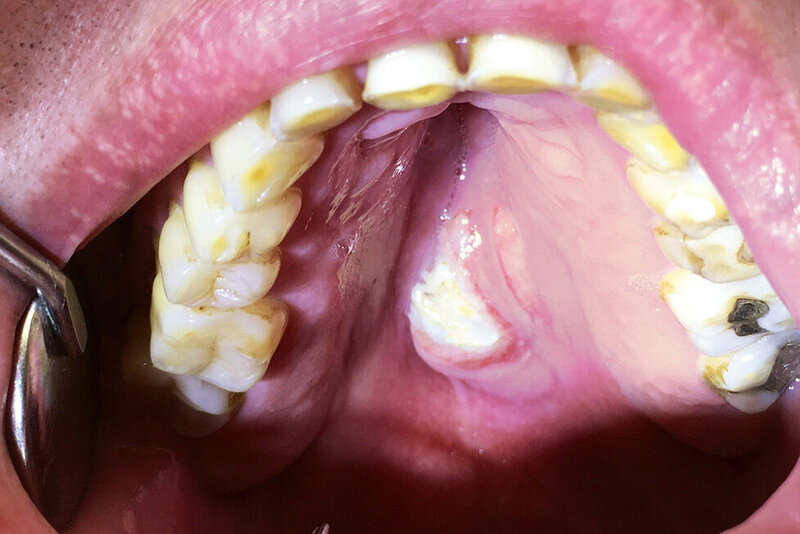

Bei der extraoralen Inspektion ergaben sich keine Besonderheiten. Intraoral zeigte sich eine etwa 3 cm große, erhabene, unverschiebliche, schmerzfreie Schwellung in der Gaumenmitte, am Übergang vom harten zum weichen Gaumen. Diese war vom Tastbefund prall elastisch, die Oberfläche ulzeriert und fibrinbelegt. Die Ränder des Befunds waren gerötet. Die Palpation der Halsregion ergab keine Auffälligkeit.

Die digitale Volumentomografie zeigte einen weichgeweblichen Tumor – bei vollständiger Erhaltung der Kontinuität des knöchernen Gaumens. Nach ausführlicher Aufklärung des Patienten wurde die Veränderung mit Verdacht auf ein pleomorphes Adenom in Lokalanästhesie vollständig exzidiert und der pathohistologischen Befundung zugeführt. Postoperativ wurde eine Verbandplatte eingebracht, unter der die Wunde sekundär granulierte. Die Heilung verlief komplikationslos. Nach vier Wochen war die Wunde vollständig epithelialisiert.